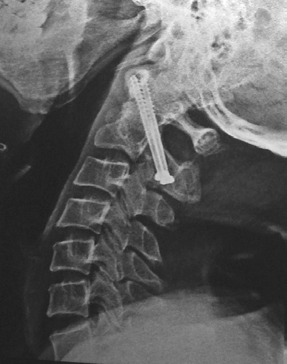

Only Screw